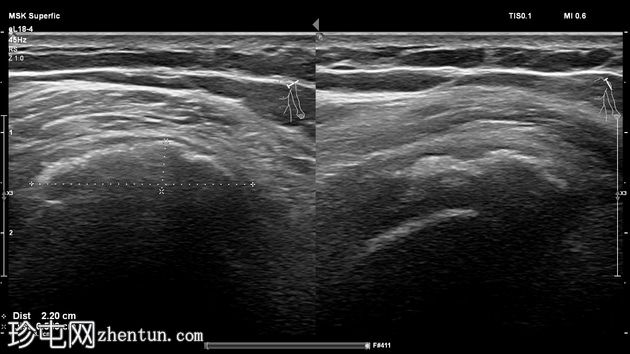

超声

横断面

侧位面

冈上肌腱可见弧形声反射,边缘呈分叶状,远端声影逐渐加重,符合钙化表现。

典型的钙化性肌腱炎超声和X线表现。肩袖是最常受累的部位,冈上肌腱受累的病例占80%,本例亦是如此。